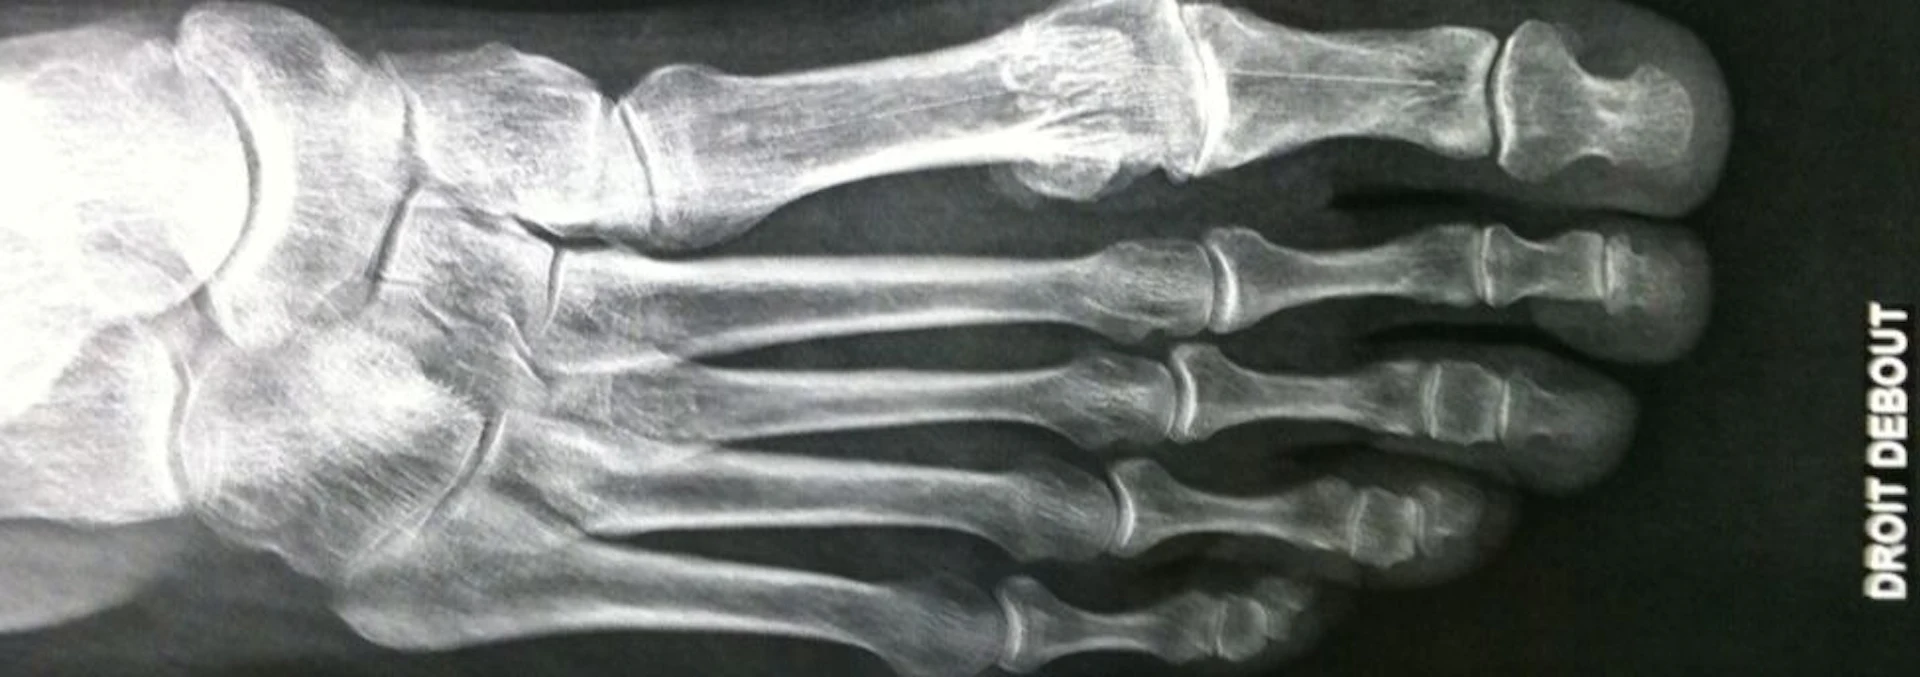

Hallux rigidus is the latin term for arthritis of the metatarsophalangeal joint of the big toe (the ball of the big toe). Strictly speaking, hallux rigidus translates “Stiff big toe”. Just like any joint, the end of the bone surfaces are covered in shock-absorbing cartilage much like the gristle at the end of a chicken drumstick. In arthritis, the cartilage wears away and bone rubs against bone, which causes pain. The big toe joint is a particularly complicated joint because there are two pea-shaped bones sitting under the big toe called the sesamoid bones which are also involved in motion.

The joint is stiff usually because there is scarring of the lining of the joint (capsule). This is coupled with extra bony spurs that form around the joint and also loss of the shock-absorbing lining of the joint (articular cartilage).

There are several reasons for the pain associated with Hallux Rigidus. It might be that the soft tissue lining of the joint (the synovium) is inflamed. Or it might be that areas of bone are rubbing or impinging on other areas of bone, or indeed a combination of these reasons.

Pain and stiffness are the predominant symptoms. Patients may feel a lumpy feeling on the top or side of the big toe, which is caused by bone spurs under the skin. Bone spurs are the body’s response to arthritis. They form as a way of stiffening the joint to protect it from further harm. The best way to think of them is much like stabilisers placed onto a child’s bicycle.